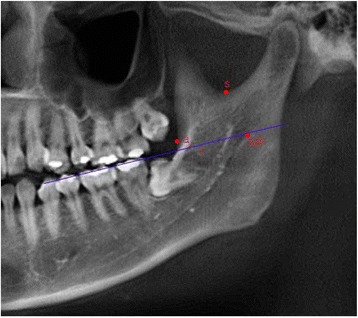

The mandibular foramen (MF) was set posterosuperior to the opening of mandibular canal. The deepest point of the anterior edge of the mandibular ramus was named ‘a’ and the lowest point of mandibular notch was named ‘s’. The extension of the occlusal plane connecting the mesio-occlusal line angle of the first premolars and the postero-occlusal line angle of the second molars was given a value of ‘l’ and used as a reference in comparing the positions of the mandibular foramen (Table 1, Fig. 1).

Reference point and line

| MF | Posteriorsuperior point of mandibular canal opening |

| a | Deepest point on anterior border of ascending ramus |

| s | Lowest point of mandibular notch |

| l | Extension line of occlusal plane |

Fig. 1.

Reference point and line